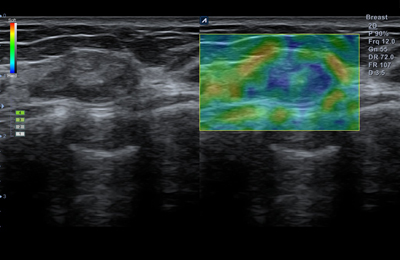

L3-12HWD

High density wide footprint linear transducer (3-12MHz)

Application:

Breast, EM, MSK, Vascular, Small Parts, Appendix